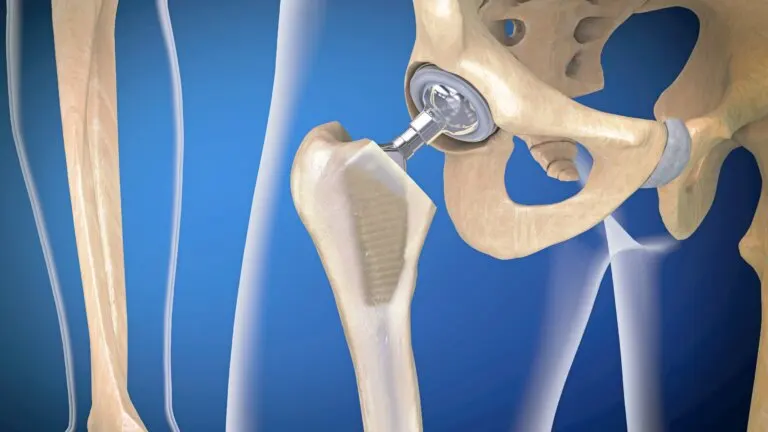

La infección de prótesis articulares es una complicación relativamente frecuente tras los reemplazos articulares. La colocación de prótesis es una cirugía muy extendida en la actualidad, que ayuda a tratar numerosas patologías relacionadas con el aparato óseo.

La mayor parte de los casos involucran prótesis de cadera o de rodilla. Aunque son procedimientos con muy buenos resultados, pueden tener complicaciones, como cualquier otra técnica quirúrgica. ¿Por qué ocurre esta infección? ¿Cuáles son sus síntomas? A continuación, resolvemos estos interrogantes.

La infección de prótesis articulares también se conoce como ‘infección periprotésica’. Se trata de una complicación que compromete tanto la zona del reemplazo articular como los tejidos adyacentes.

Artroplastia es el nombre médico de este procedimiento. Según información de la Clínica Universidad de Navarra, en España se realizan alrededor de unas 30 000 intervenciones de este tipo al año. Es un procedimiento seguro que, en la mayoría de casos, produce una mejoría notable en la calidad de vida del paciente.

Las articulaciones más propensas a ser sustituidas por una prótesis son la cadera y la rodilla.